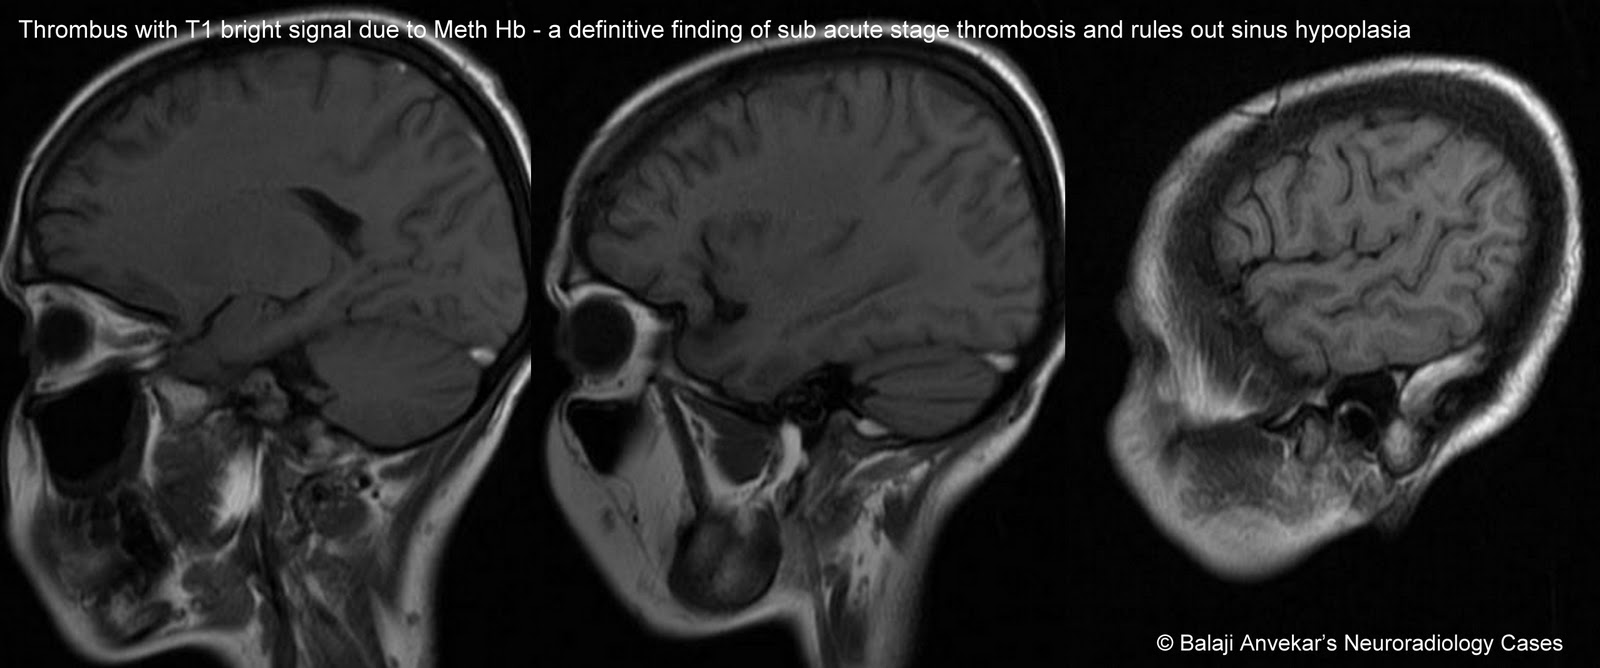

Дегенерация синуса

Дегенерация синуса 83 фото